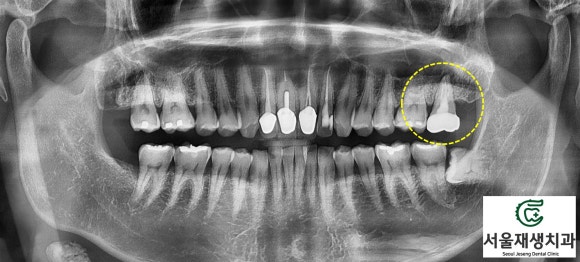

육안으로 환자분의 증상을 체크한 뒤,

영상검사를 시행했습니다.

치아들의 단체사진인 파노라마를 먼저 촬영하여 문제 치아를 찾아냅니다.

보아하니 왼쪽 위 맨 끝에 있는 어금니군요.